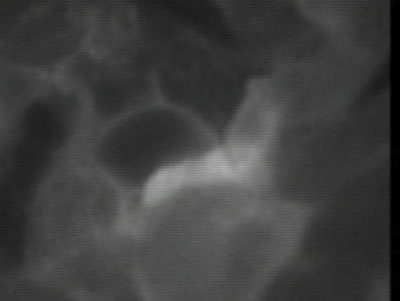

術中吻合